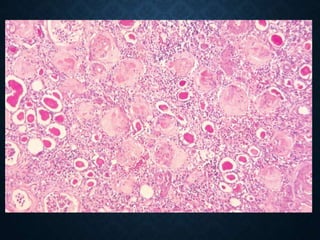

FATTY CHANGE OF THE

KIDNEYS

• Fat deposition in renal tubular cells, with increased

reabsorption, and due to the enormous passage of

lipids through damaged glomeruli, usually in

glomerulonephritis or severe hypoxia

• Macroscopic: enlarged kidneys, soft consistency and

yellow color.

• Histological: fat droplets in the tubular epithelium